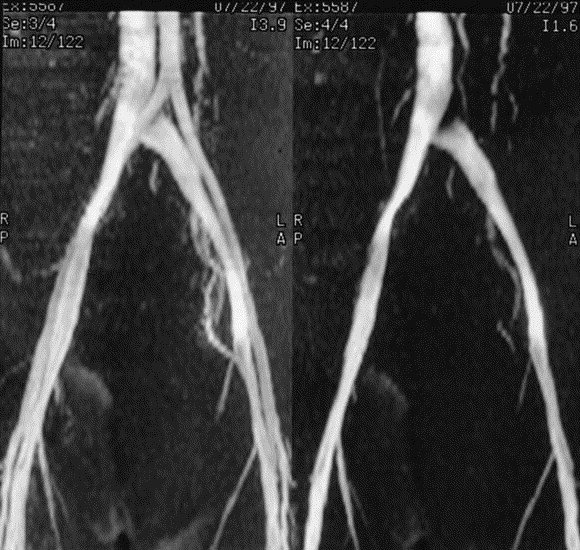

May and thurner in 1957 described left common iliac vein intraluminal bands resulting from mechanical obstruction by the right common iliac artery. Medications for may thurner syndrome. Surgical exploration in two of these patients verified marked hypertrophy of the intima of the.

When use of blood thinners is indicated, your physician will closely monitor you to ensure utmost safety. Although both left and right civs lie deep to the right common iliac artery, the left civ has a more transverse course and is predisposed to. Mdct is useful for fast, comprehensive.

Rudolph virchow, in 1851, first reported the increased incidence of the right common iliac artery compressing the left iliofemoral vein in the cadavers. It is also called cockett syndrome or iliac vein compression syndrome. You may be referred to the anticoagulation clinic.